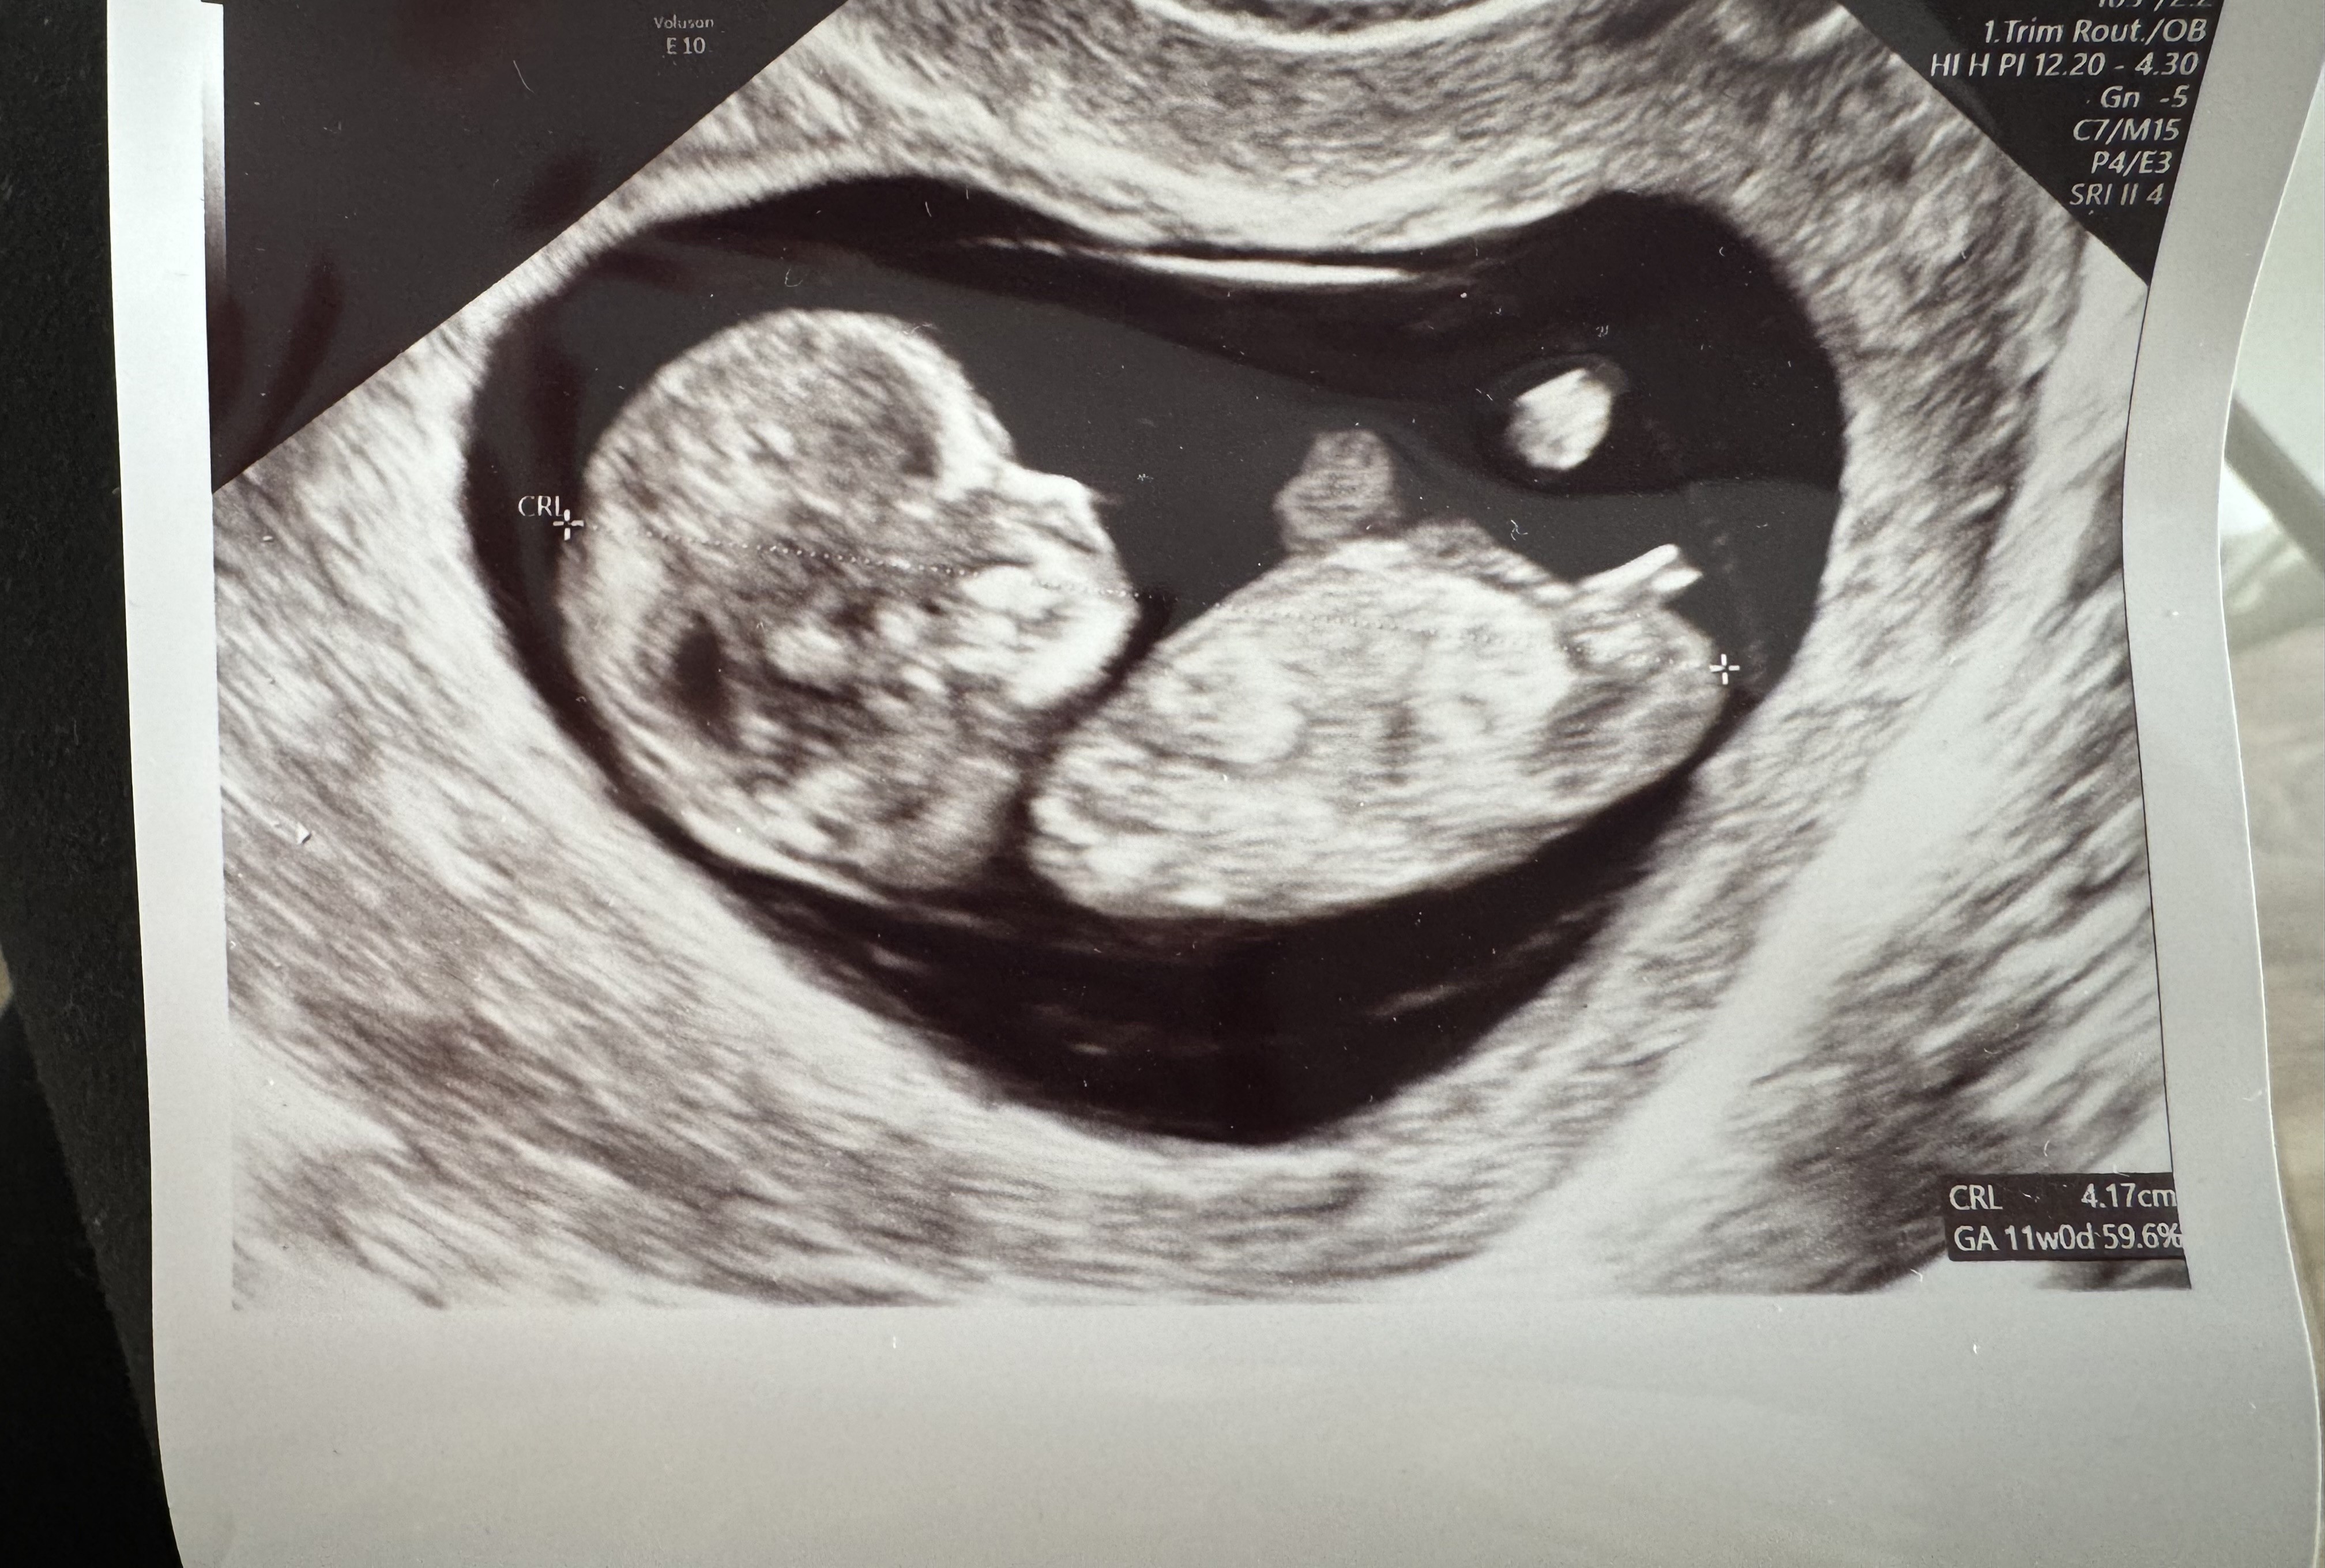

Dla mnie też bardziej dziewczynka 🤔 zobacz jak to u mnie wyglądało -

Na pierwszym chłopiec na drugim dziewczynka (równolegle do kręgosłupa)

• IMG_6770.jpeg

IMG_6770.jpeg

1,5 MB · Wyświetleń: 180